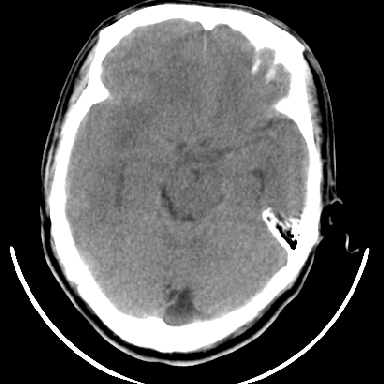

标题: CT6056:脑出血(血管畸形?) [打印本页]

标题: CT6056:脑出血(血管畸形?)

m 40突发头痛左侧偏瘫3小时

考虑高血压性脑出血,依据:

1是高血压性脑出血的好发部位,形态呈肾形,是高血压性脑出血的常见形状

2增强时占位效应加重了,考虑出血还没有停止

3病灶周围水肿不是太厉害,一般肿瘤出血水肿多非常明显

4病灶周围的‘软组织’影没有明显的强化

5至于脑血管畸形引起的出血,暂时没有看到明显的畸形血管影,也不太支持

支持右侧基底节脑出血

右侧基底节区脑出血.

支持右侧基底节区(主要为外囊区)原发性脑出血。

另附部分资料:“血液溢出血管外形成血肿,其内含有大量血红蛋白、血浆白蛋白,球蛋白,因这些蛋白对x线的吸收系数高于脑质,故ct呈现高密度阴影,ct值达40~90h,最初高密度灶呈非均匀一致性,中心密度更高,新鲜出血灶边缘不清。基底节区血肿多为“肾”型,内侧凹陷,外侧膨隆,因外侧裂阻力较小,故向外凸,其它部位血肿多呈尖圆形或不规则形”

术中抽出40ml陈旧血液,血肿底部似见一条索血管影